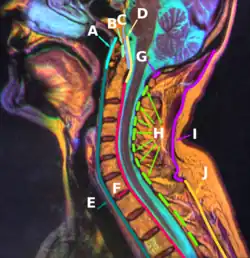

![]() Membrana tectoria, transverse, and alar ligaments. ("Transverse ligament" and "vertical portion" visible intersecting at center.) | |

The cruciate ligament of the atlas (cruciform ligament) is a cross-shaped (thus the name) ligament in the neck forming part of the atlanto-axial joint. It consists of the transverse ligament of atlas, a superior longitudinal band, and an inferior longitudinal band.

The cruciate ligament of the atlas consists of the transverse ligament of the atlas, a superior longitudinal band, and an inferior longitudinal band.[1][2] The superior longitudinal band connects the transverse ligament to the anterior side of the foramen magnum (near the basilar part) in the occipital bone of the skull. The inferior longitudinal band connects the transverse ligament to the body of the axis bone (C2).[1]